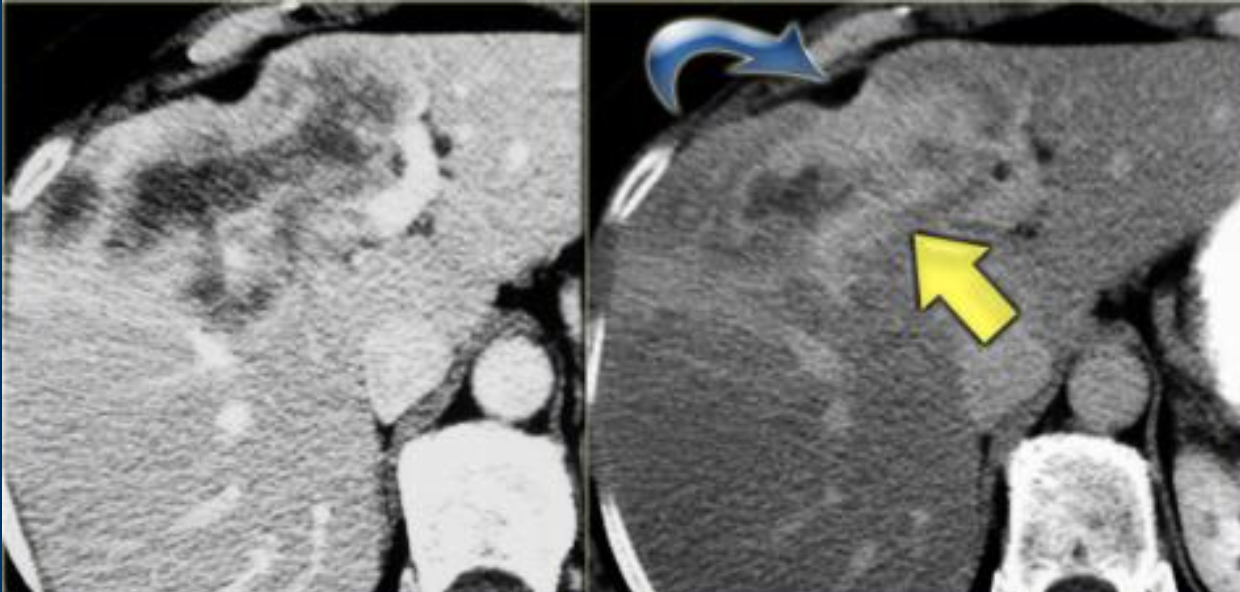

Imaging findings of Intrahepatic Cholangiocarcinoma

where geographically is it more common?

- More common in asia than in the USA

- Adenocarcinoma from the intrahepatic bile ducts

- Biliary ductal dilatation distal to tumour

- lesions have irregular borders with infiltrative margins

- Delayed peripheral to central enhancement as a result of fibrosis and hypovascularity

- Capsular retraction and vascular invasion.